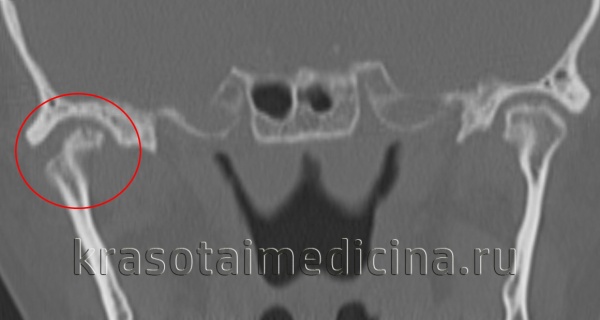

• Лучший диагностический критерий:

о Выраженное сужение или отсутствие суставного пространства, неровные края суставных поверхностей с фиброзными или костными «мостиками»

(Слева) На сагиттальной реформатированной КЛКТ определяется анкилоз левого мыщелка. Мыщелок склерозирован, суставное пространство отсутствует в зоне слияния. Височная кость неровная, склерозированная. Суставная ямка уплощена, суставное возвышение отсутствует.

(Справа) На панорамной рентгенограмме определяется костный анкилоз левого ВНЧС. Суставное пространство не визуализируется, форма мыщелка плохо различима. Венечный отросток удлинен, антегониальная вырезка углублена.